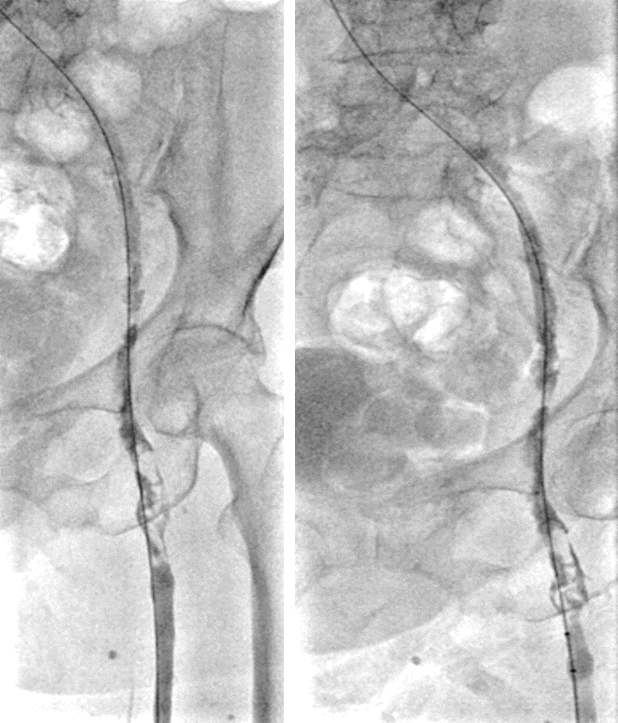

左足背静脉造影:左小腿深静脉、腘静脉通畅,股浅静脉、股总静脉及髂静脉血栓

左腘静脉穿刺置鞘,对近端血栓行AngioJet喷注尿激酶后吸栓,吸栓后股浅静脉恢复通畅

复查造影:股深静脉内血栓,股总静脉血流瘀滞,左髂静脉狭窄行PTA

Simon导管翻山后导丝进入股深静脉,造影明确股深静脉血栓范围

股深静脉吸栓后通畅,于左髂静脉置入14*80mm支架,复查造影血流均通畅